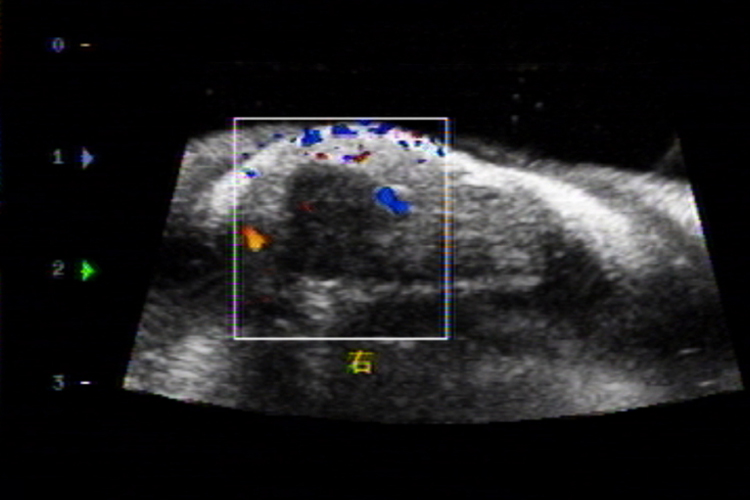

手指关节腱鞘炎的超声诊断表现为腱鞘壁增厚,呈低回声或无回声,腱鞘内可见积液或无明显积液,腱鞘炎时腱鞘内一般无血流信号。